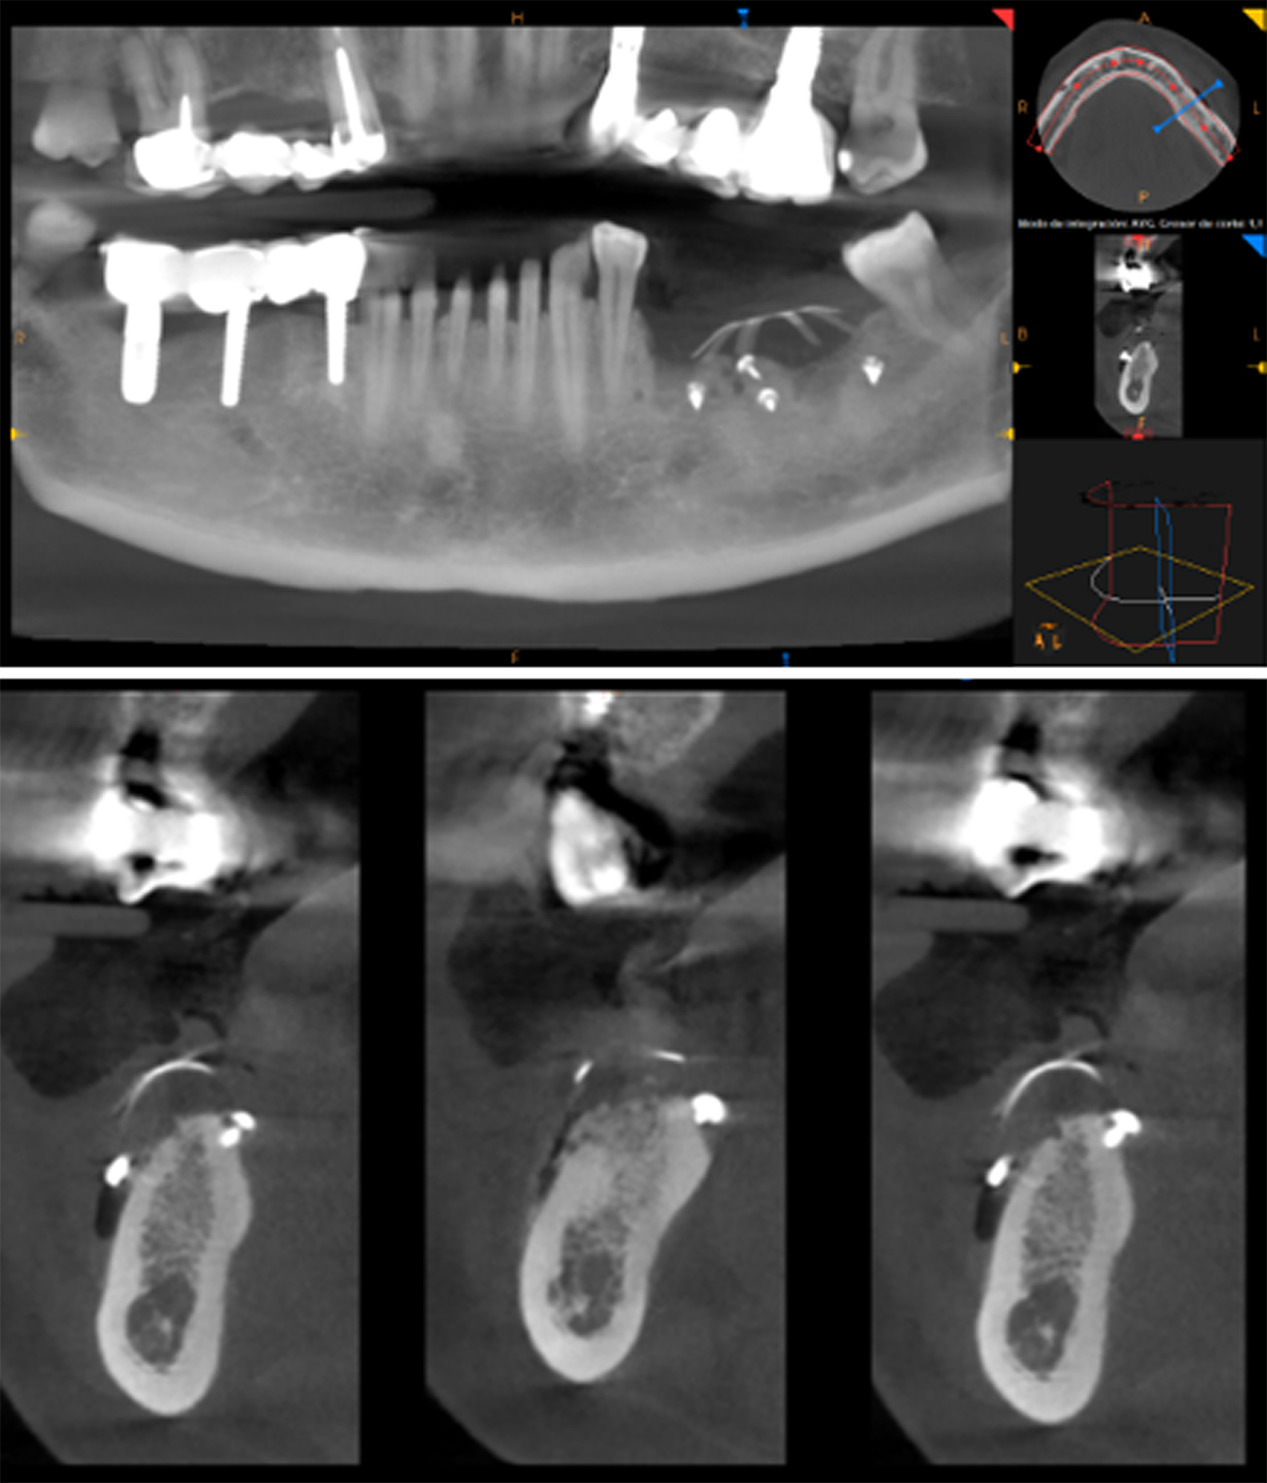

At 6 months postoperative, CT scans showed optimal bone density with mature characteristics and optimal thickness/height for adequate three-dimensional implant placement (Figure 14). Removal of the titanium-reinforced membrane at 3 months postoperative did not appear to have a significant impact on the regenerative process. A full-thickness flap was created for implant placement, revealing a good bone appearance with visible vascularization, rim thickness, and maturation (Figure 15). The implants were placed, achieving favorable primary stability and optimal three-dimensional ridge placement due to the thickness/height achieved from the regenerative procedure (Figure 16). Periapical radiographs following placement of the healing screws confirmed favorable bone-implant interaction (Figure 17). A panoramic radiograph prior to crown placement showed evident hard tissue stability in the regenerated area (Figure 18). Finally, panoramic and periapical radiographs at 24 months postoperative showed healthy, stable bone regeneration and ideal placement of the implants and bridge (Figure 19).

Figure 14. CT scan at 6 months postoperative showed optimal bone density with mature characteristics and optimal thickness/height for adequate three-dimensional implant placement